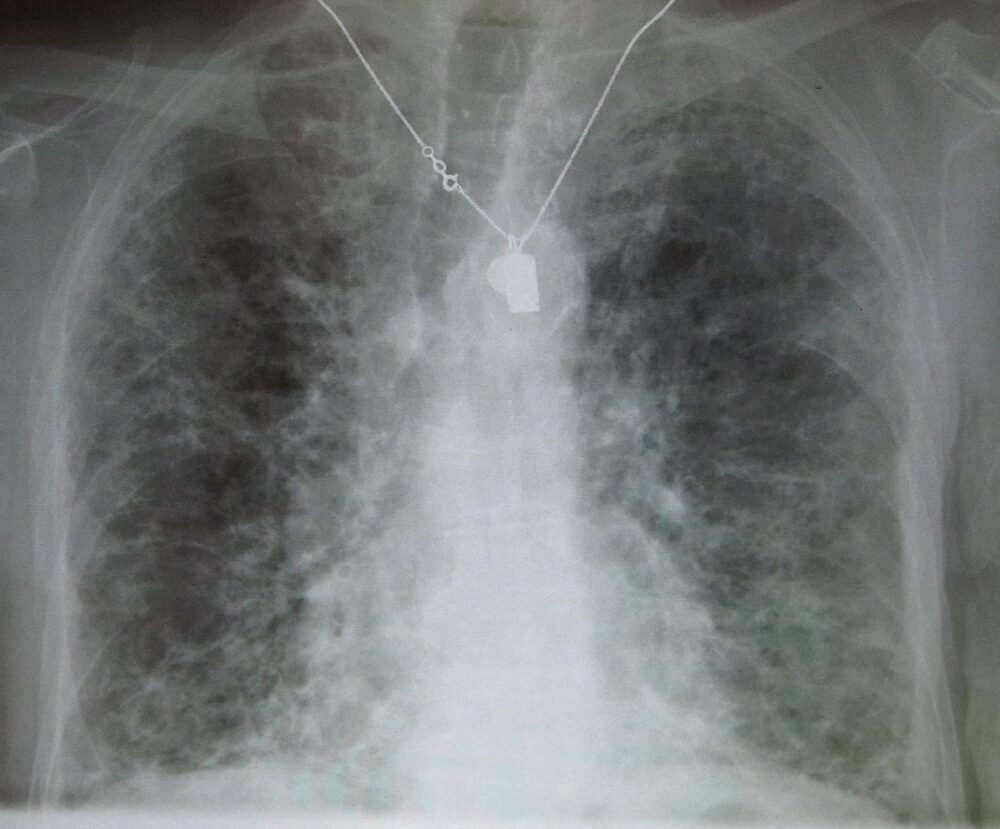

Ma quanto è importante la partecipazione di tutti gli stakeholder nella ricerca? “È importante, ancora prima che nella ricerca, per la presa in carico dei pazienti- ha risposto Di Marco alla Dire- perché la ricerca è funzionale al trattare i pazienti. Le fibrosi polmonari sono una malattia complessa, che però non viene considerata alla stregua dell’oncologia, pur avendo gli stessi impatti devastanti di un tumore. Quindi è importante che gli stakeholder lavorino assieme per portare avanti il bisogno di avere una diagnosi precoce e di una presa in carico a 360 gradi, con tutti i componenti della filiera della salute a partire dal medico di base, dallo pneumologo al reumatologo fino al radiologo, ma anche e soprattutto delle associazioni dei pazienti, che possono davvero supportare questo miglioramento della vita dei pazienti”.